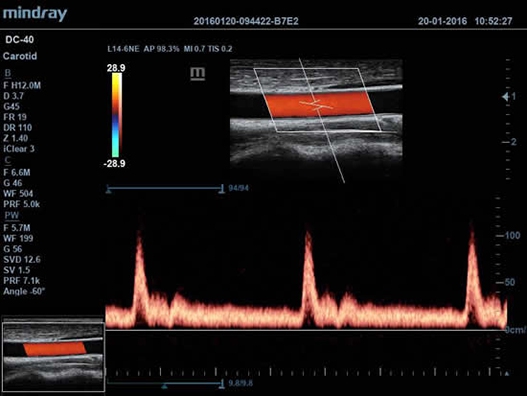

• Auto IMT Package – измерения и анализ толщины комплекса интимамедии (КИМ) сонной артерии;

• Функция Auto IMT автоматически измеряет толщину комплекса интима-медиа.